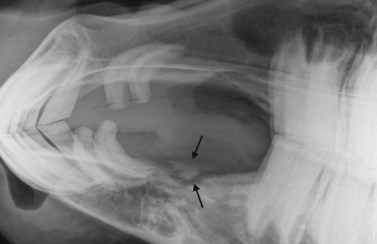

Dorsoventral projection (Figs 13.1213.13)

This view is quite easy to obtain in the sedated horse and is particularly useful for visualizing the ventral conchal sinus, nasal cavities, and nasal septum. Additionally, it can be used for evaluating maxillary/mandibular fractures; bony distortion of the maxilla associated with periapical infection of the rostral cheek teeth or intra-sinus masses. Laterally or medially displaced teeth and fractured maxillary teeth (particularly sagittal fractures) can also be visualized with this view; however, these abnormalities should be apparent during a thorough oral examination. The extremely dense bone of the hemimandibles makes it almost impossible to evaluate normally positioned mandibular cheek teeth using this projection.

An increased exposure is required for this projection compared to those used for lateral or lateral-oblique views of the skull. The X-ray beam is directed perpendicular to the dorsal plane of the head (which runs parallel to the hard palate) with the cassette held parallel with the ventral mandible and positioned as caudally as possible (Fig. 13.12). Because the mandibular cheek teeth rows are so close together (anisognathia), even a small degree of obliquity obscures one nasal cavity, ventral conchal sinus, and maxillary cheek teeth row and prevents accurate comparison of left and right maxillary sinus opacity; therefore, great care must be taken to ensure that the head is absolutely straight and the beam perpendicular to the dorsal plane. The centering point is in the midline of the dorsal aspect of the head at the level of the rostral aspect of the facial crests. Collimation of the primary beam should include the left and right lateral extents of the skull, the caudal aspects of the bony orbits and the diastemata, rostrally (Fig. 13.13).